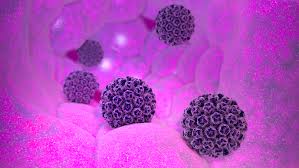

Μία νέα συνδυασμένη θεραπεία, που συμπεριλαμβάνει την ανοσοθεραπεία pembrolizumab, εγκρίθηκε για διάθεση στους Ευρωπαίους πάσχοντες από προχωρημένο καρκίνο του νεφρού.

Ο προχωρημένος καρκίνος του νεφρού είναι ένας επιθετικός καρκίνος. Για την αντιμετώπισή του εγκρίθηκε από την Ευρωπαϊκή Επιτροπή ένας νέος συνδυασμός φαρμάκων. Πρόκειται για τον συνδυασμό της ανοσοθεραπείας pembrolizumab με τον αναστολέα axitinib (αξιτινίμπη), που εγκρίθηκε ως θεραπείας 1ης γραμμής.

Η έγκριση αφορά τους ασθενείς με νεφροκυτταρικό καρκίνωμα ανεξαρτήτως ομάδας κινδύνου (IMDC Risk Group).

Το νεφροκυτταρικό καρκίνωμα είναι ο πιο συχνός καρκίνος του νεφρού. Αντιπροσωπεύει το σχεδόν 90% των περιστατικών της νόσου. Ο συγκεκριμένος καρκίνος του νεφρού είναι περίπου δύο φορές συχνότερος στους άνδρες απ’ ό,τι στις γυναίκες.

Ο καρκίνος του νεφρού διαγνώσθηκε το 2018 σε 403.000 ανθρώπους σε όλο τον κόσμο. Κόστισε επίσης τη ζωή 175.000 ασθενών. Στην Ευρώπη εκτιμάται ότι το 2018 διαγνώσθηκαν 136.500 νέες περιπτώσεις και σημειώθηκαν 54.700 θάνατοι.

Μείωση του κινδύνου θανάτου

Η ευρωπαϊκή έγκριση του συνδυασμού pembrolizumab-axitinib βασίστηκε στα αποτελέσματα της κλινικής μελέτης KEYNOTE-426. Η μελέτη αυτή κατέδειξε σημαντική βελτίωση της συνολικής επιβίωσης στους ασθενείς που έλαβαν τον συνδυασμό.

Ειδικότερα, η KEYNOTE-426 που ήταν μία μελέτη Φάσης 3, έδειξε ότι ο παραπάνω συνδυασμός μείωσε κατά 47% τον κίνδυνο θανάτου σε σύγκριση με τη δραστική ουσία σουνιτινίμπη (sunitinib) σε ασθενείς με προχωρημένο νεφροκυτταρικό καρκίνωμα.

Επίσης κατέδειξε βελτίωση ως προς την επιβίωση χωρίς εξέλιξη της νόσου (PFS) καθώς και ως προς το ποσοστό αντικειμενικής ανταπόκρισης (ORR) σε σύγκριση με τη σουνιτινίμπη.

«Ο προχωρημένος καρκίνος του νεφρού είναι ένας από τους πιο επικίνδυνους τύπους καρκίνου. Η πλειονότητα των ασθενών αποβιώνουν εντός πενταετίας από τη στιγμή της αρχικής διάγνωσης», δήλωσε ο επικεφαλής ερευνητής Thomas Powles, καθηγητής και διευθυντής του Κέντρου Barts Cancer Center.

Και συνέχισε: «Είναι ενθαρρυντικό το γεγονός ότι τώρα μπορούμε να προσφέρουμε στους ασθενείς στην Ευρώπη τον συνδυασμό pembrolizumab με αξιτινίμπη ως θεραπευτική επιλογή πρώτης γραμμής».

«Σημαντικό ορόσημο»

«H έγκριση από την ΕΕ του συνδυασμού pembrolizumab με αξιτινίμπη για τη θεραπεία του προχωρημένου νεφροκυτταρικού καρκινώματος σηματοδοτεί ένα σημαντικό ορόσημο στις προσπάθειές μας έναντι αυτής της επιθετικής νόσου», δήλωσε ο Δρ. Scot Ebbinghaus, αντιπρόεδρος, κλινικός ερευνητής στα ερευνητικά εργαστήρια της MSD (MSD Research Laboratories).

«Η παροχή μίας επιπλέον θεραπευτικής επιλογής ως θεραπεία 1ης γραμμής είναι μια ιδιαίτερα σημαντική εξέλιξη για τους ασθενείς με τη νόσο. Αντανακλά τη δέσμευσή μας να διευρύνουμε τη χρήση του pembrolizumab σε τομείς όπου υπάρχουν ακόμα ανεκπλήρωτες ιατρικές ανάγκες», πρόσθεσε.

Η έγκριση επιτρέπει την εμπορική διάθεση του συνδυασμού pembrolizumab με αξιτινίμπη και στα 28 κράτη μέλη της Ε.Ε., συν την Ισλανδία, το Λιχτενστάιν και τη Νορβηγία.

Στη μελέτη KEYNOTE-426 συμμετείχαν 861 ασθενείς από 16 χώρες του κόσμου.